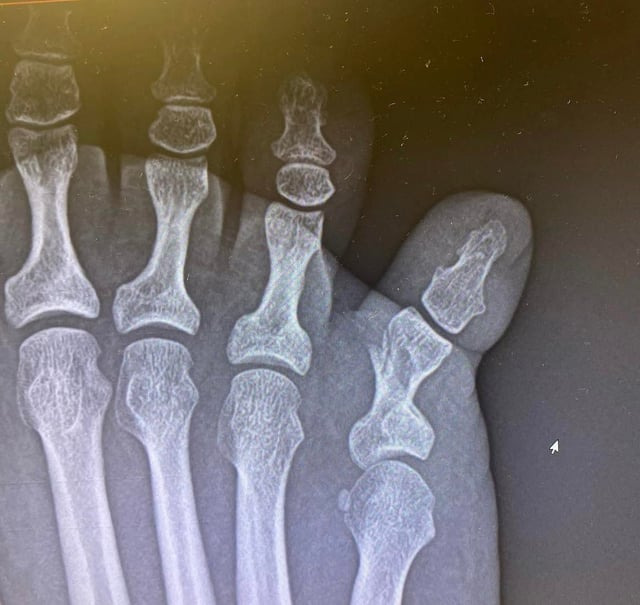

의료적으로 새끼발가락 골절은 X-ray 촬영을 통해 뼈의 연속성이 끊어진 상태가 확인될 때 확진됩니다. 단순 실금 수준의 미세골절부터 명확한 골절선이 보이는 경우까지 범위가 다양합니다.